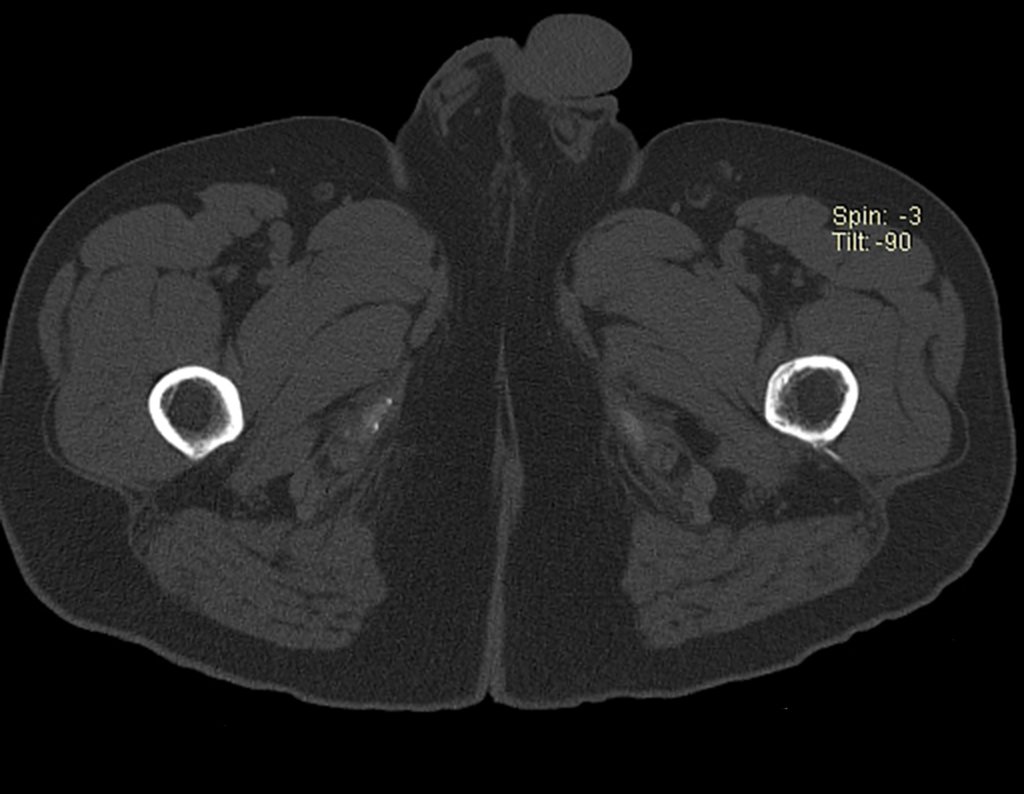

Repetiu a radiografia e realizou tomografia em 20/02/2015, figuras 10 a 13.

A tomografia do tórax de abril, as radiografias e a tomografia do quadril de maio de 2015 podem ser analisadas nas figuras 33 a 38.

O paciente retorna em 22 de julho de 2015, com queixa de dor quando passa da posição sentada para em pé, dor à rotação do quadril e claudicação. Os exames de imagem, da ressonância de 18 de julho se 2015, são analisados nas figuras 39 a 59.